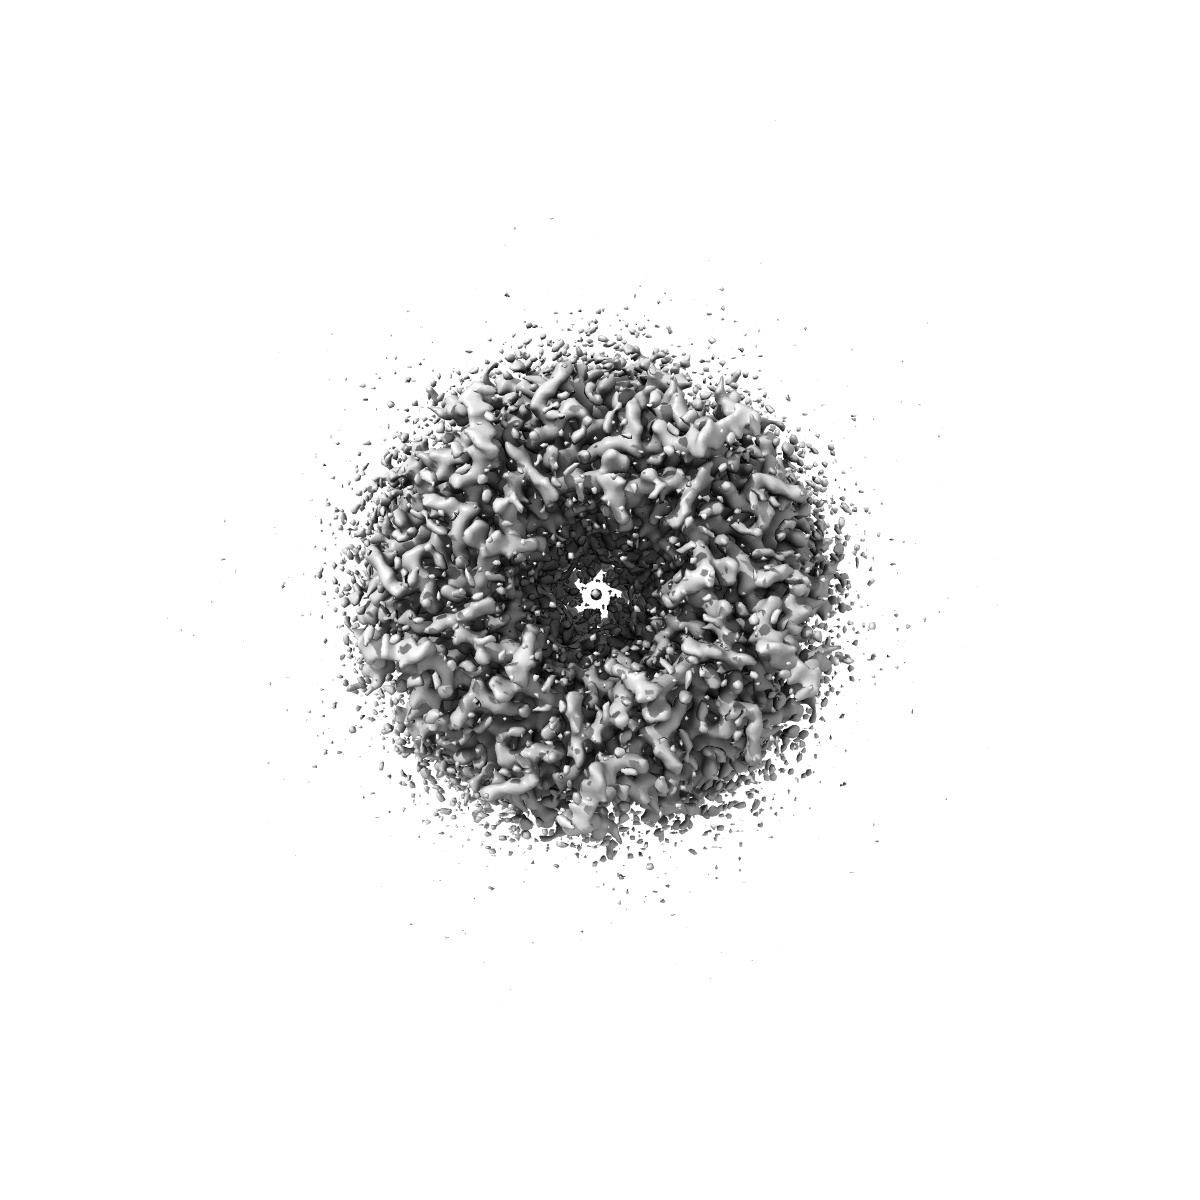

CryoEM structure of human rho1 GABAA receptor in complex with (R)-GABOB in the desensitized state

Sample: human rho1 GABAA receptor

Cryo-EM structures of rho 1 GABA A receptors with antagonist and agonist drugs.

Fan C , Cowgill J , Howard RJ , Lindahl E

(2025) Nat Commun , 16 , 7077 - 7077